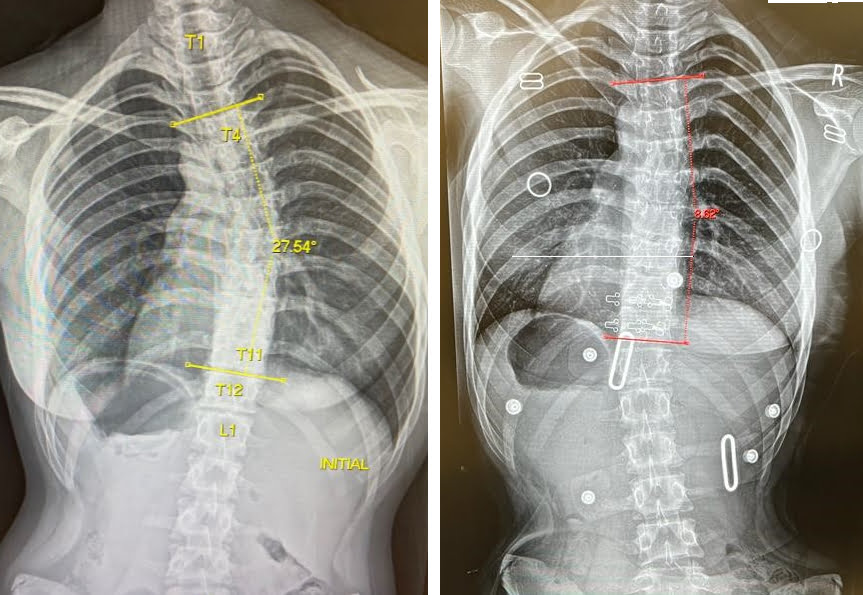

حتى أولئك الذين يعانون من اعوجاج العمود الفقري الشديد، حيث تزيد زاوية كوب عن 40 درجة، فقد استجابوا جيدًا لطريقه العلاج التي تعتمد على أحزمه الجنف تشينو-جينسينجن وبرنامج العلاج الطبيعي الذي يتبع مبادئ العلاج الطبيعي في شروث.

قبل و بعد

قبل و بعد